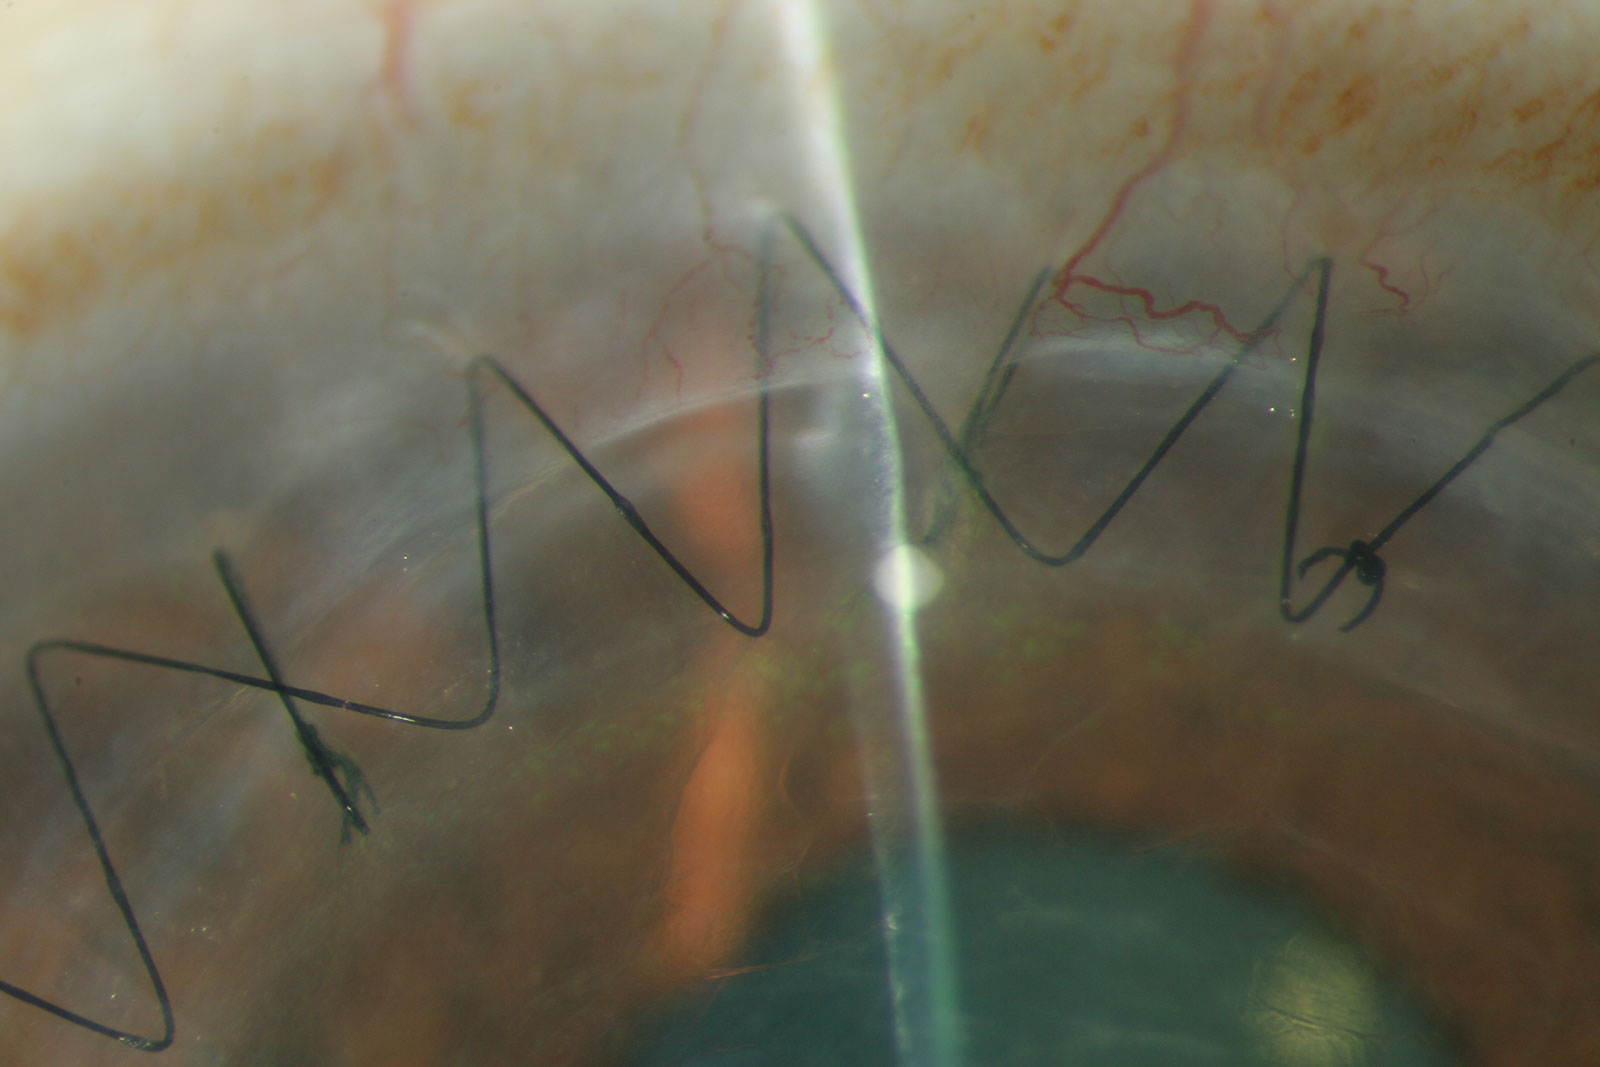

The cornea is the clear, transparent tissue at the front-most part of the eye, functioning as the window to the eye. The cornea, together with the natural lens inside the eye, refract (or bend) light coming from the outside world and refocus them onto the retina for a clear image. Therefore, any disease or process that interferes with the cornea may interfere with this light-bending process and blur one’s vision.

Corneal diseases result from many causes ranging from infectious, inflammatory, structural, and traumatic origins. A few examples are illustrated below. If you have a corneal disease that adversely affects your sight, please see our fellowship-trained cornea specialist for a medical consultation. Some corneal diseases may cause irreversible vision loss if not treated in a timely manner.